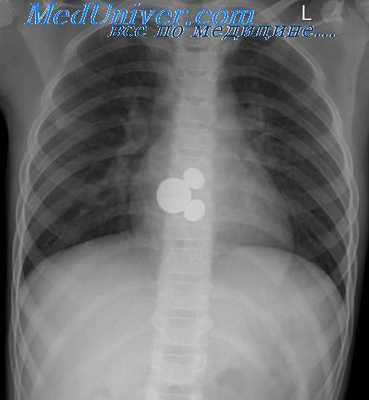

Суммарная экспозиция ПИ определяется проникающим первичным и рассеянным вторичным рентгеновским излучением. При уменьшении или увеличении вклада любого из этих типов излучения соответствующим образом изменяется и экспозиция ПИ. Пока хотя бы минимальное количество первичного рентгеновского излучения проникает сквозь все ткани, недоэкспонированное или переэкспонированное в пределах двухкратного отклонения изображение может быть нормализовано, что позволит избежать повторного исследования (рис. 1 и 2). В таблицах ниже перечислены способы определения по рентгенограмме, а также причины и способы корректировки недостаточной или избыточной экспозиции.

РИСУНОК 1 Рентгенограммы таза. В центре первого ряда представлена рентгенограмма оптимального качества, которая была скопирована и обработана с использованием различных «окон» отображения, чтобы продемонстрировать, как будут выглядеть рентгенограммы при оптимальном значении кВп и приемлемом диапазоне мАс. Второй ряд показывает, как будут выглядеть рентгенограммы первого ряда после нормализации. Если величина экспозиции недоэкспонированной или переэкспони-рованной рентгенограммы укладывается в данное 400% окно, то повторять исследование не нужно. Повторная рентгенография оправдана только при выходе величины экспозиции за пределы этого окна. Если получена рентгенограмма, похожая на правую или левую в первом ряду, то причина этого заключается не в экспозиции ПИ, а в методике обработки. РИСУНОК 2 Рентгенограммы таза. В центре первого ряда представлена рентгенограмма оптимального качества, которая была скопирована и обработана с использованием различных «окон» отображения, чтобы продемонстрировать, как будут выглядеть рентгенограммы при увеличении или уменьшении кВп на 15% (двухкратное изменение экпозиции) по сравнению с оптимальным значением. Второй ряд демонстрирует, как будут выглядеть рентгенограммы первого ряда после нормализации. Если величина экспозиции недоэкспонированной или переэкспонированной рентгенограммы при изменении кВп находится в пределах двухкратного отклонения от оптимального значения, то повторение исследования не оправдано.